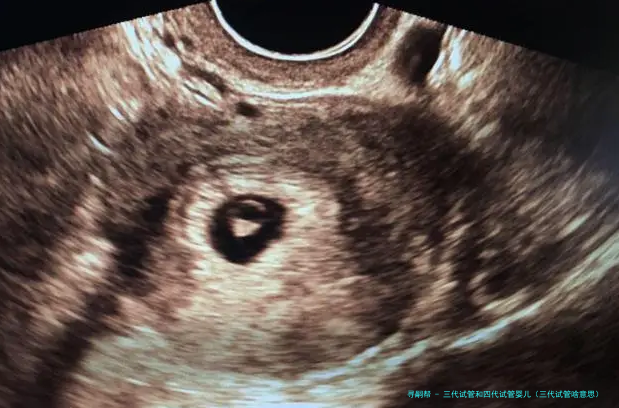

试管婴儿的医学术语称:胚胎转移技术-胚胎移植,其过程是女的一方先使用药物促排卵,再从卵巢内拿出卵子,男方拿出精子,在实验室将精子、卵子结合培育成胚胎,然后又将胚胎转至子宫腔内,令其着床、妊娠。

“试管婴儿”的完整名称叫做“试管受孕和胚胎移植术”(试管婴儿(IVF)-ET),是一种今世诊疗技术。原理是将卵子、精子分别拿出体外,在人工受控制条件下完成精卵结合,成活后再受精卵移植到母亲身内,着床发育。

试管婴儿道理 “试管婴儿”其实不是真正在试管里长大的婴儿,而是从卵巢内拿出若干个卵子,在实践室里使之们与男方的精子结合,形成胚胎,然后挪动转移胚胎到子宫内,让它位于妈妈的子宫内着床、妊娠。

试管婴儿的道理实际上其实不繁复。在正常情况下,受孕过程是由精子进入女的一方身体内,到达输卵管,在输卵管的壶腹部与卵子碰见结合成受孕卵,然后在子宫着床、生长。